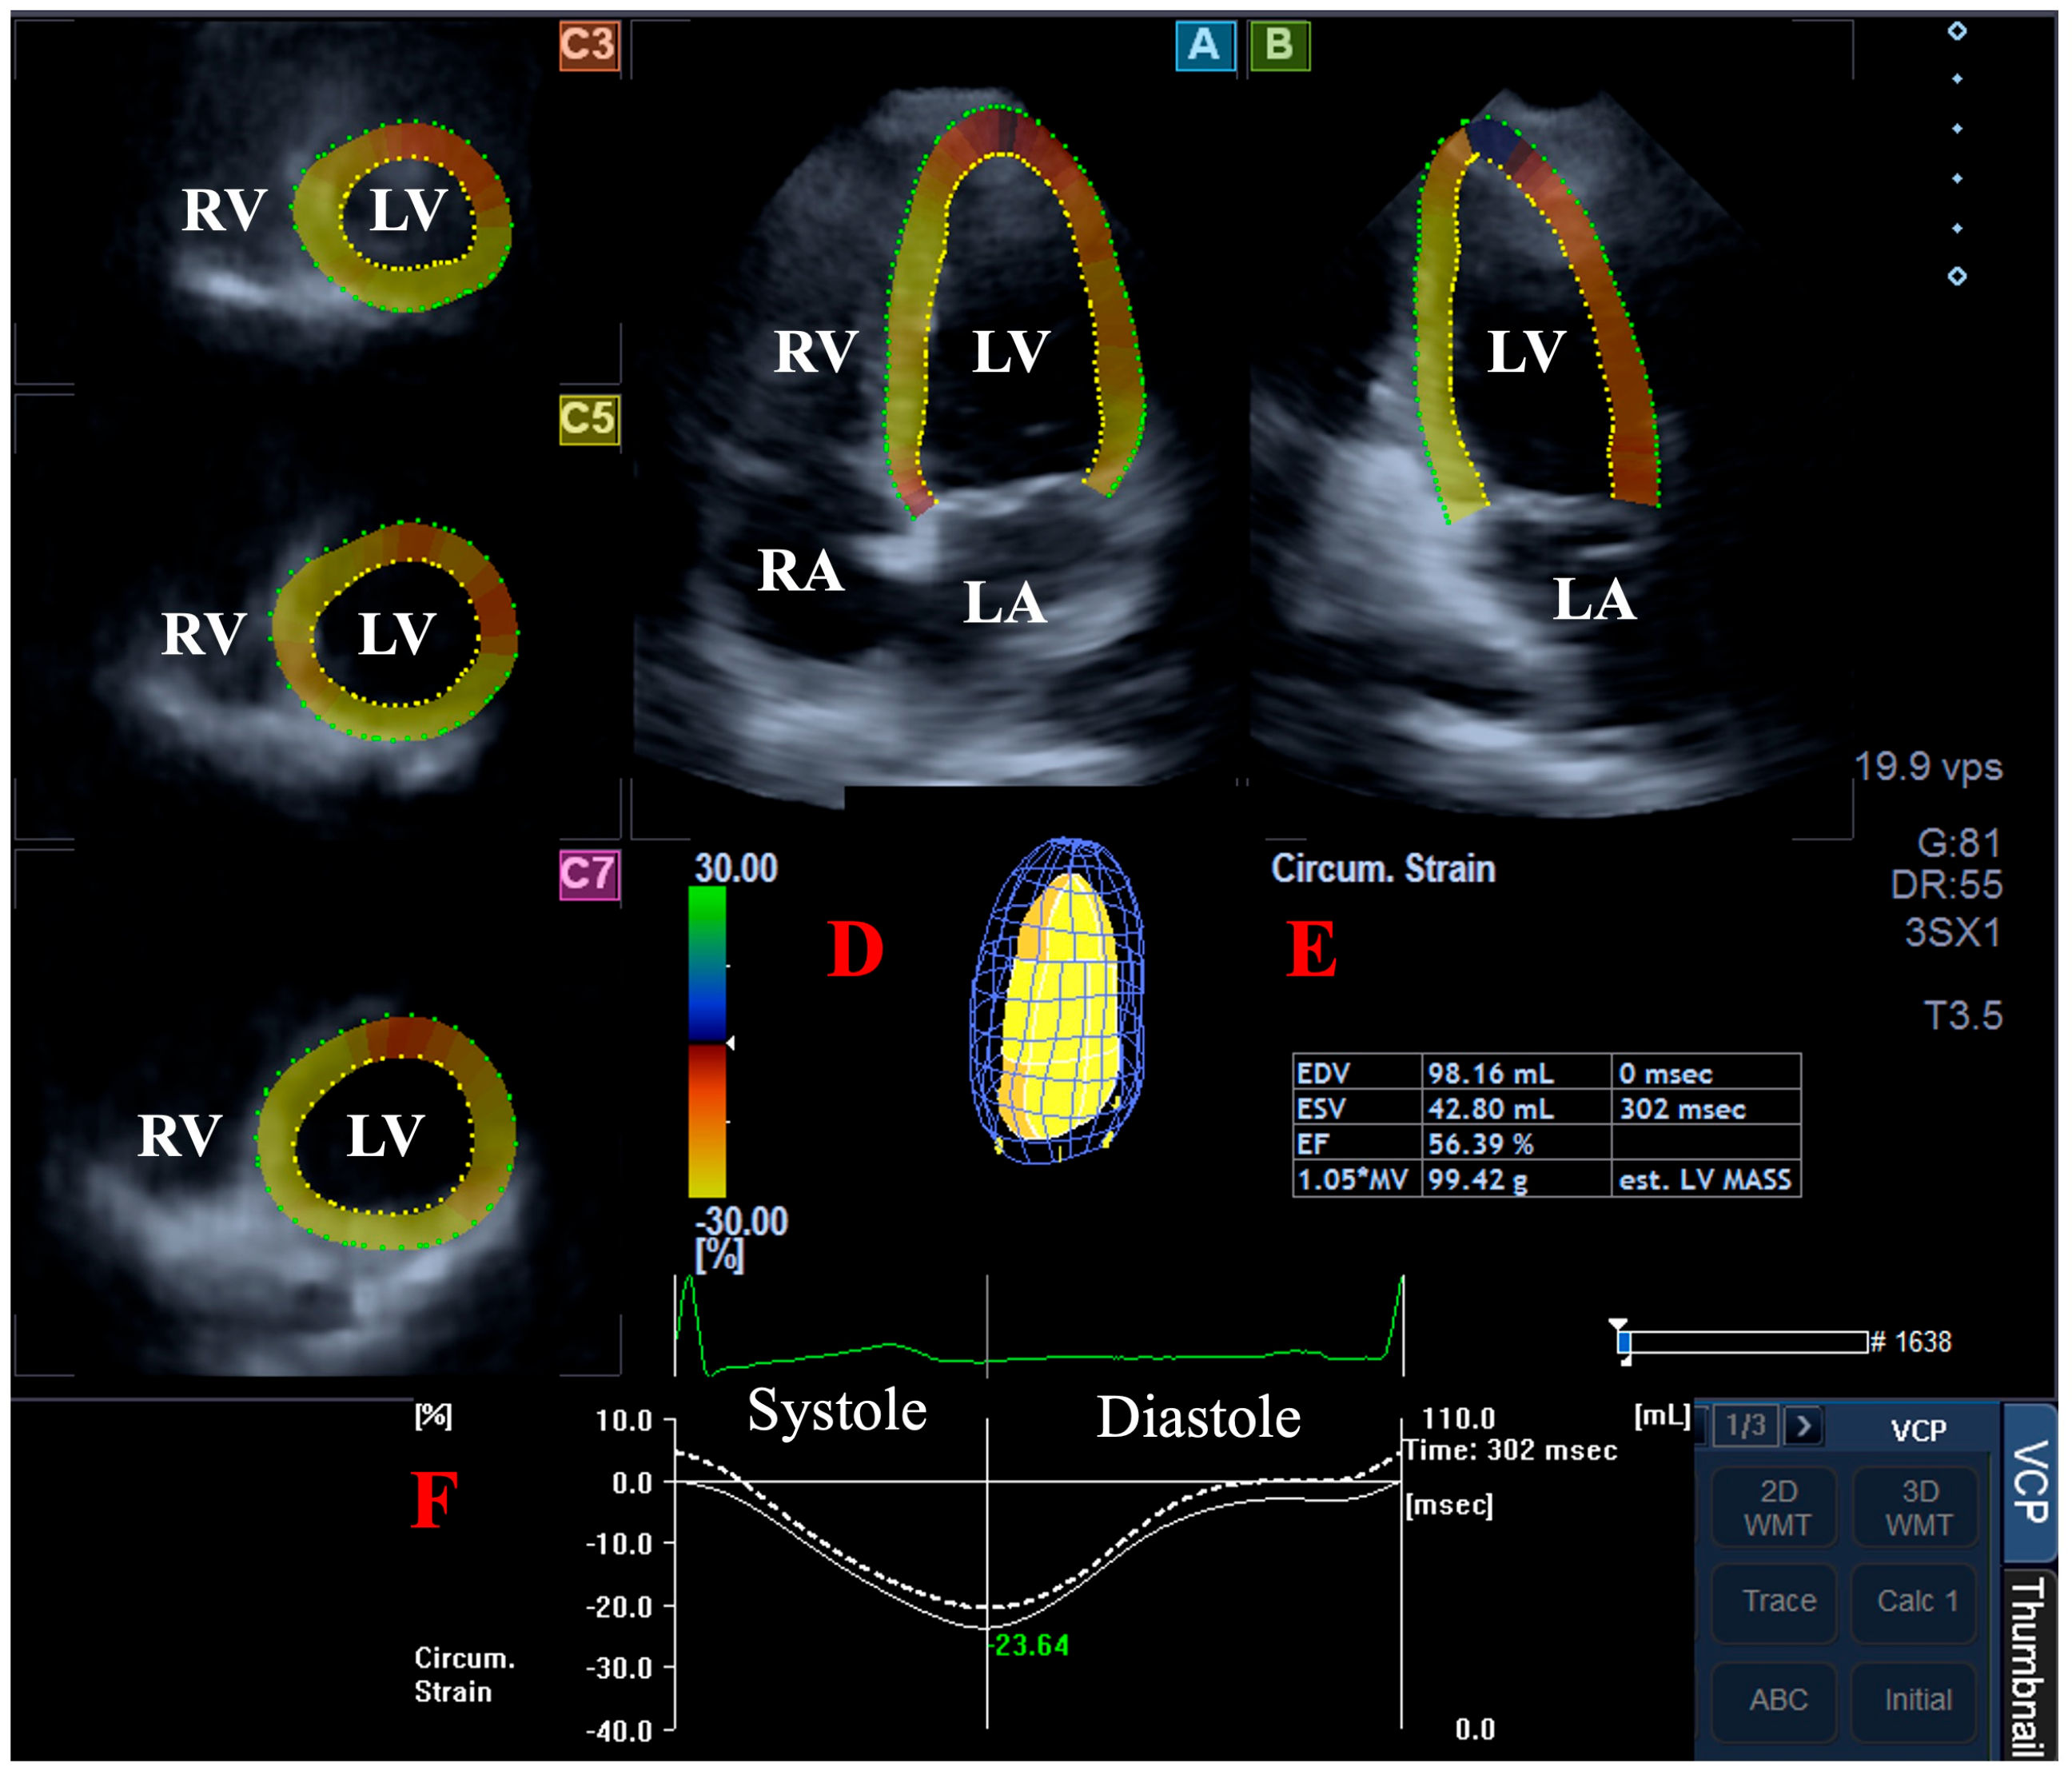

2.3. Three-Dimensional Speckle-Tracking Echocardiography--Derived Data Acquisition

2.4. Three-Dimensional Speckle-Tracking Echocardiography-Derived LV Volumetric Measurements

2.5. Three-Dimensional Speckle-Tracking Echocardiography-Derived Assessment of Peak LA Global Strains

- LA-GRS—LA global radial strain representing LA thinning/thickening;

- LA-GCS—LA global circumferential strain representing LA widening/narrowing;

- LA-GLS—LA global longitudinal strain representing LA lengthening/shortening;

- LA-G3DS—LA global 3D strain, combination of all unidirectional LA strains;

- LA-GAS—LA global area strain, combination of LA circumferential and longitudinal strains.